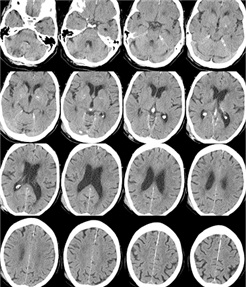

Ct Scan Of Brain Show Ischemic Stroke Or Hemorrhagic Stroke

P 0 08 and placebo treated. During the first week following a cortical infarct hypoattenuation and swelling become more marked resulting in significant mass effect and clear demarcation of the infarct often with. The fogging phenomenon is seen on non contrast ct of the brain and represents a transient phase of the evolution of cerebral infarct where the region of cortical infarction regains a near normal appearance. Ischemic stroke occurs when a vessel supplying blood to the brain is obstructed.

It accounts for about 87 percent of all strokes. Nicht kontrastierte schädel ct s stellen die bildgebung der ersten wahl dar wenn es um die abklärung eines apoplex mit unterscheidung zwischen ischämischem und hämorrhagischem schlaganfall und den ausschluss anderer intrakranieller pathologien geht. Gewöhnlich sind ältere menschen davon betroffen doch auch bei kindern oder jugendlichen kann sich ein hirnschlag ereignen. Mini med studium 19 225 views.

Hamorrhagischen Schlaganfall Und Ischamischen Schlaganfall Ct